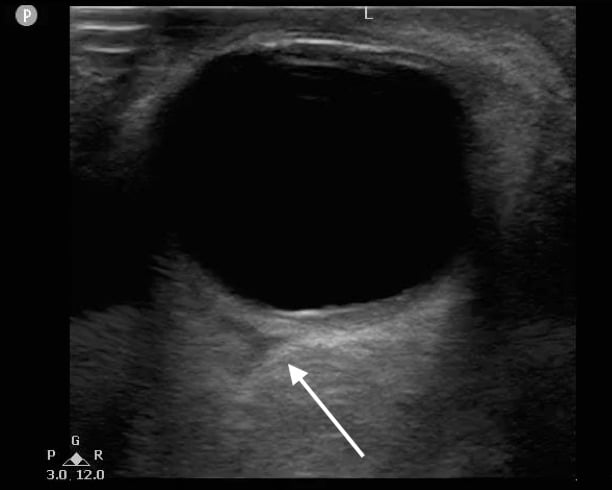

- Figure 12. Triangular hypoechoic area (white arrow) suggestive of retrobulbar hematoma also known as “Guitar Pick Sign.”